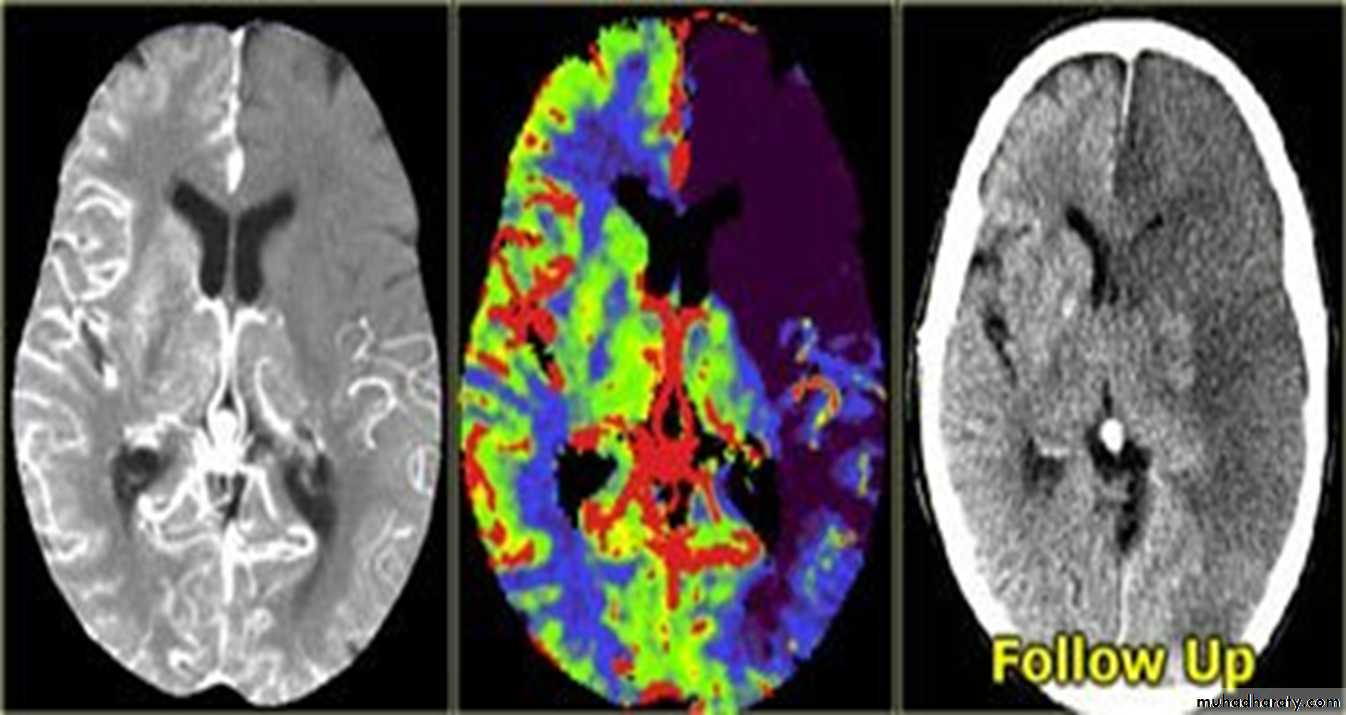

ACUTE INFARCTION

* wedge shape hypo density area.* Shifting of the midline & frontal horn

Chronic infarction

Hypo density area(pore encephalic cyst)Dilated ventricle